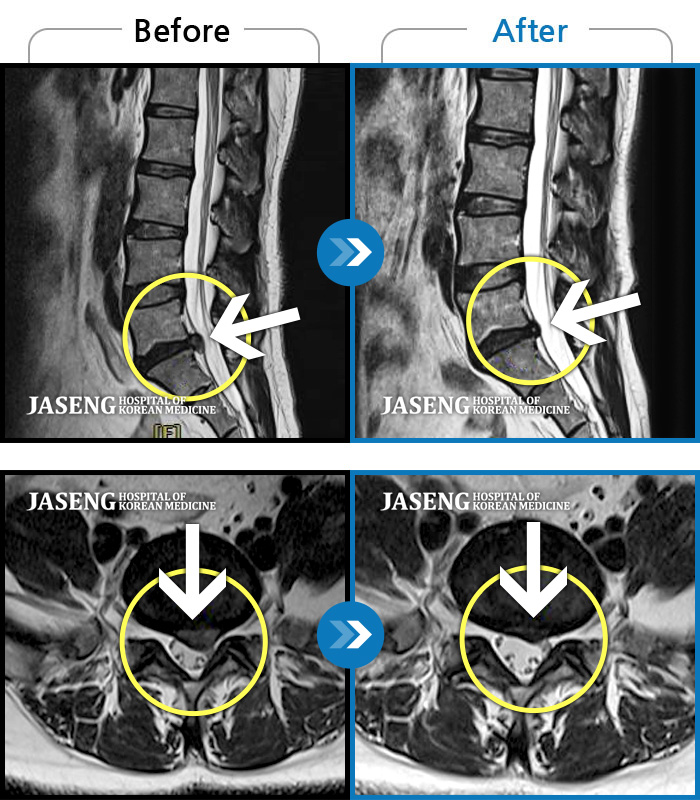

허리디스크

광주 · 장영우 원장

좌측 허리 통증으로 허리를 반듯이 펴고 서있기 힘들어 내원하셨습니다.

촬영시기

2024.08.12 ~ 2025.02.26

2025.03.07